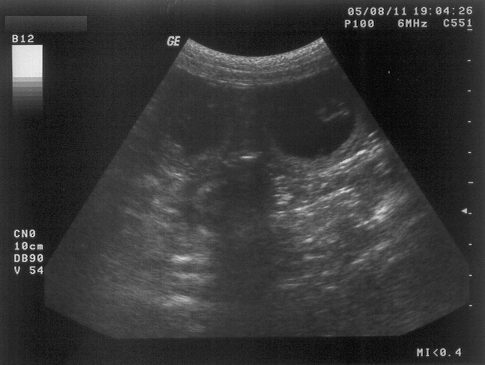

11.08.2005

So ... nun steht es definitiv fest (als ob ich es nicht schon die ganze Zeit gewusst hätte).

Ich bin schwanger und meine Welpen sollen im September (ca. 15.09.2005) zur Welt kommen.

Im Augenblick bin ich noch ein wenig sprachlos, aber sobald das sich gelegt hat, werde ich hier ein wenig mehr berichten.

Ein "bewegtes" Ultraschallbild findet ihr übrigens hier (Ladezeiten beachten und abwarten)